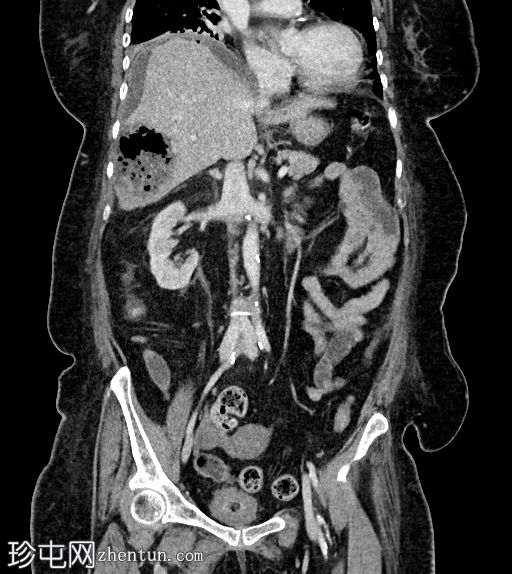

冠状位增强(C+)门静脉期

静脉期

7.jpg

肝段 6 和 7 可见多房性积液,呈环状强化

积液内可见多个气体腔

破入肝包膜下间隙,可见肝包膜下积液及气体腔

壁层腹膜与前腹壁之间可见另一局灶性积液

肝段 7 的肝内胆管局灶性扩张(0.3cm),内含气体腔

其他肝内胆管和肝外胆管均正常

胆囊缺失,可能由于既往胆囊切除术所致

无游离液体。

双侧肾皮质囊肿

轻度右侧胸腔积液伴邻近肺不张